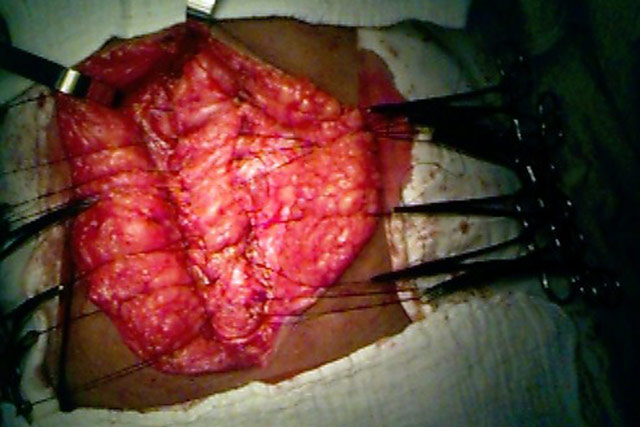

Hérnia Incisional

Fechamento do peritôneo em jaquetão.

Os bordos da aponeurose não se

encontravam, havia muita tensão.

Colocação de tela para não haver

tensão na sutura da aponeurose.